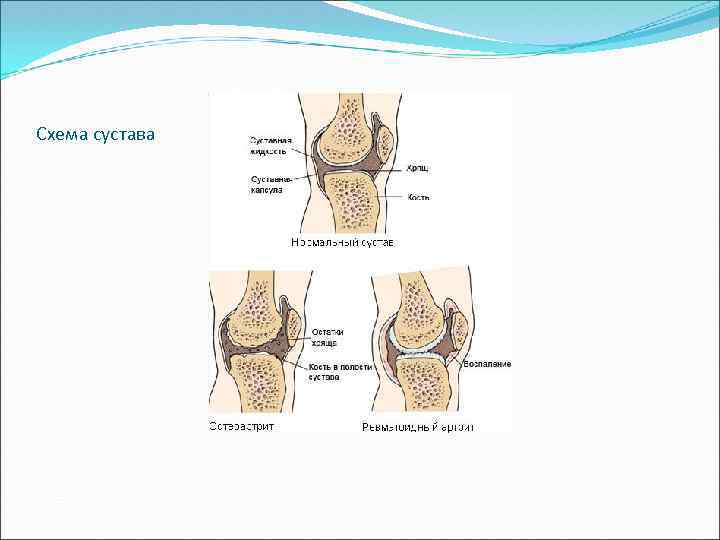

Схема сустава

Схема сустава